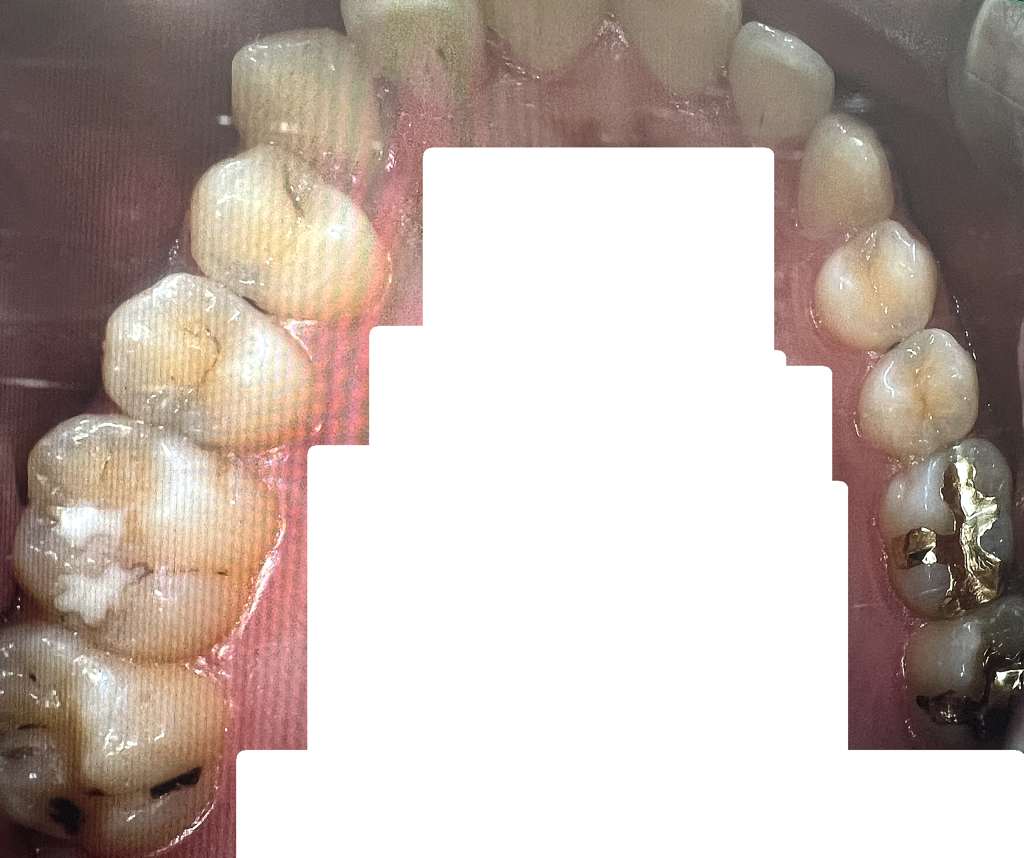

엑스레이 및 구강사진으로 충치진단

어떤 치아를 어떤 치료해야할지 알려주세요

인접면 - 레진 인레이

다른곳 크라운 등

• 3번 째 사진

치아 사이에 즉, 인접면 충치가 다수 있으신거 같습니다. 저정도면 진행되는 충치이니 치료를 하시는게 좋을것같습니다.